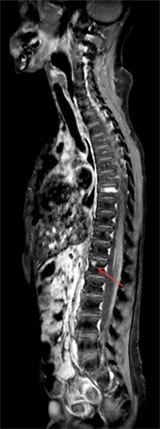

Spine, post-contrast, T1w mDIXON TSE – water Only image with FOV 450mm,

with red arrow depicting a small lesion